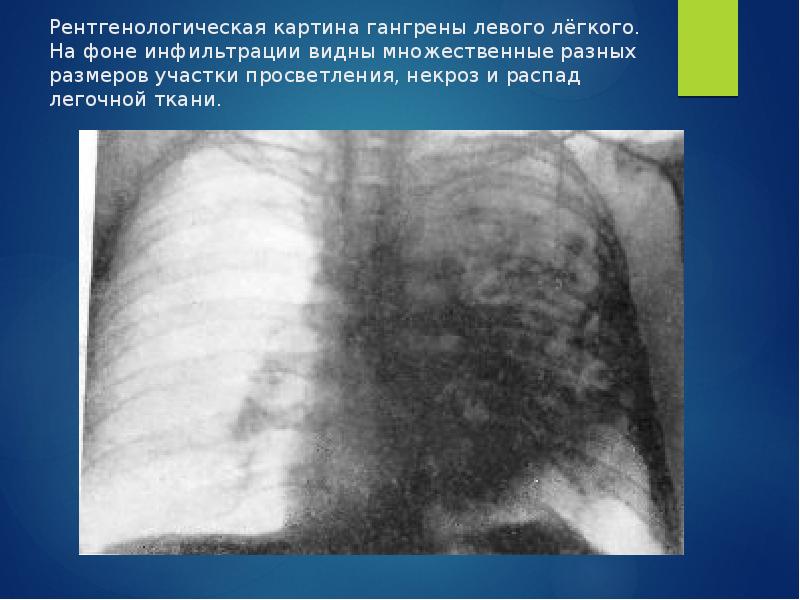

Бактериальная деструкция легких у детей презентация - 88 фото